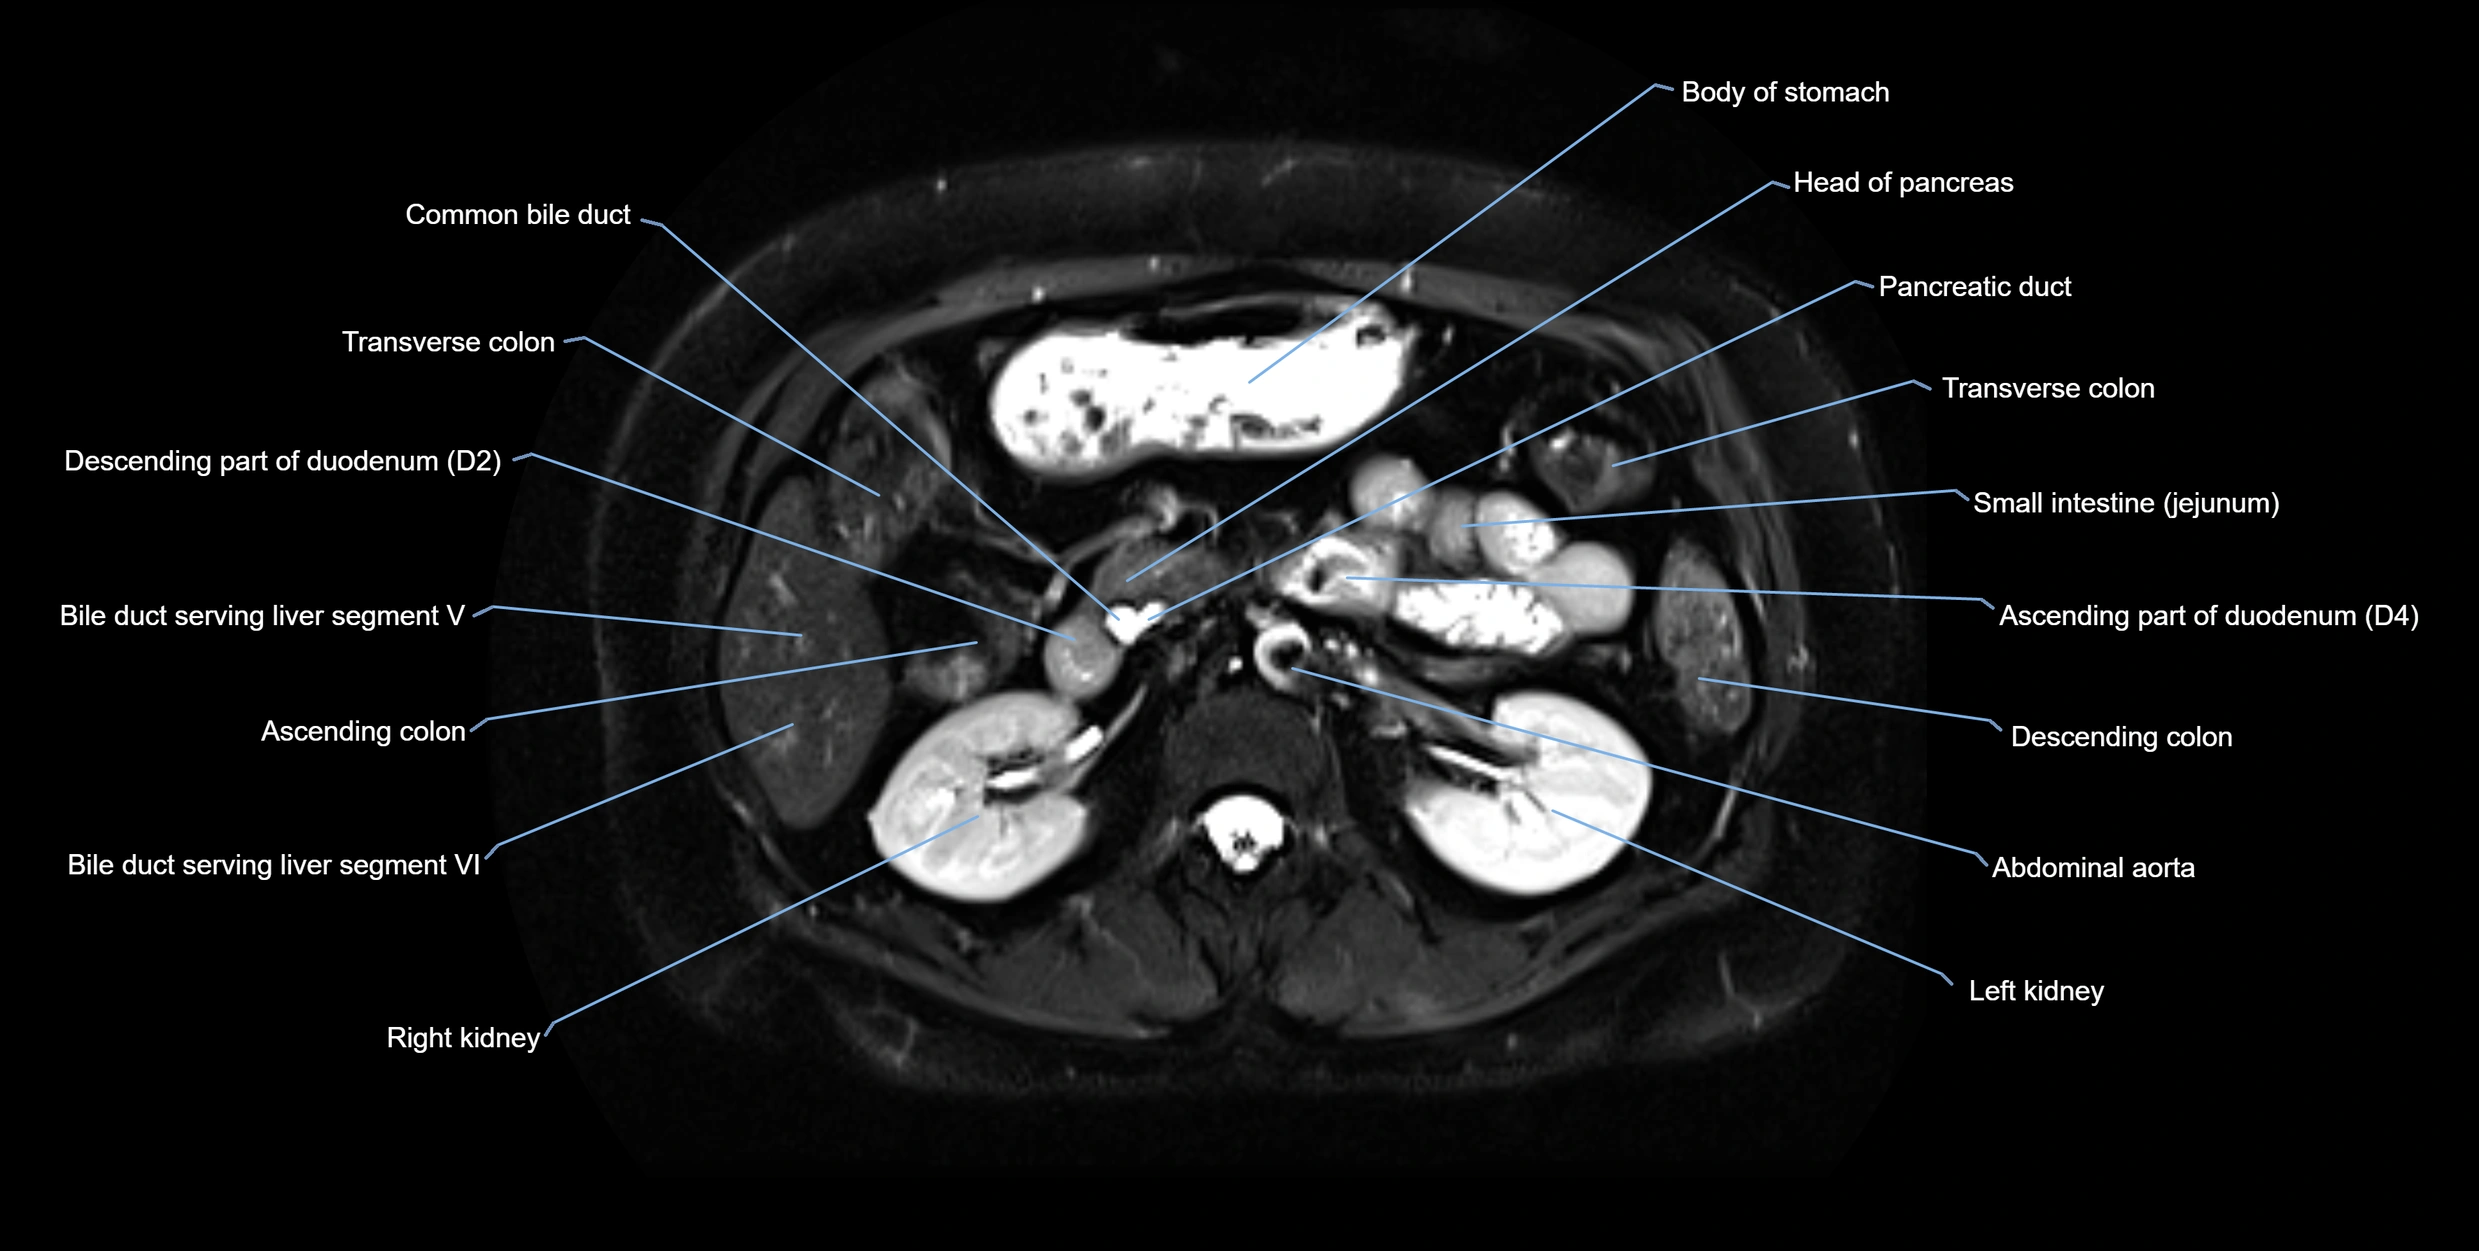

• Accessory duct: bright, thin linear structure in pancreatic head

• Stones, strictures, or air bubbles appear as dark filling defects

• Excellent for rapid evaluation of duct patency

MRI image

image